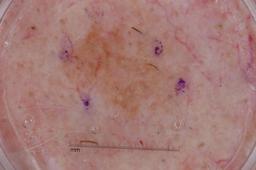

{

"age_approx": 60,

"anatom_site_general": "posterior torso",

"concomitant_biopsy": true,

"dermoscopic_type": "contact non-polarized",

"diagnosis_1": "Benign",

"diagnosis_2": "Benign epidermal proliferations",

"diagnosis_3": "Lichen planus like keratosis",

"diagnosis_confirm_type": "histopathology",

"image_type": "dermoscopic",

"lesion_id": "IL_0224481",

"melanocytic": false,

"sex": "female"

}